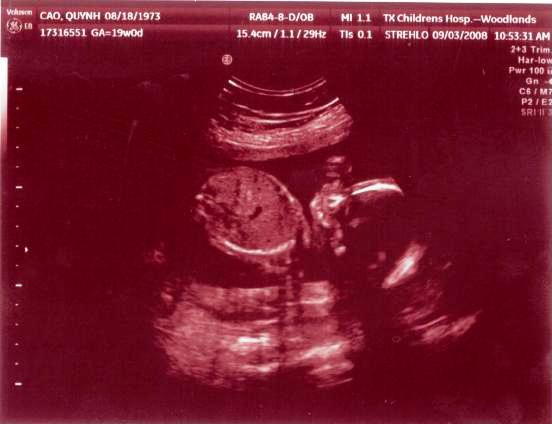

Ngày 11/28/1999 Ba Mẹ có nhau, lúc đó con ở đâu ha? Ngày 5/27/2008, con đây rồi!!! Mới được 2 tuần, là hạt nhân nhỏ xíu trong bụng Mẹ thôi Ngày 6/4/08, lần đầu tiên Ba Mẹ nghe tim con đập, 124 nhịp/phút. Mẹ sung sướng nhìn con. Còn Ba thì rơm rớm nước mắt, hihi!! Ngày 7/8/2008, con được 11 tuần rồi, bắt đầu có tay chân rồi đây... 1 tuần sau tay chân con đã dài ra rồi, lẹ ghê... ...biết nhào lộn vòng vòng nữa, mới nằm úp giờ nằm ngửa rồi. Ngày 9/3/2008, Mẹ chưa muốn biết con là trai hay gái vì muốn bất ngờ, nhưng rồi cuối cùng cũng không đợi được... ...hihi, cục cưng của Ba Mẹ là con trai. Con trai miệng bự giống Ba.  19 tuần là mắt mũi miệng đầy đủ hén. Từ khi biết có con, Mẹ nhờ Ba chụp hình hai mẹ con mình. Cái này là lúc con được 2 tháng trong bụng Mẹ.. ...24 tuần, con bắt đầu cựa quậy lung tung mỗi ngày... ...36 tuần, có lúc Ba Mẹ tưởng đã mất con nhưng con vẫn lớn giỏi ngoan... ..39 tuần, con nặng quá rồi nhưng Mẹ vẫn muốn con ở trong đó thêm chút nữa cho lớn lớn... Ba thì nôn gặp con quá, ngày nào Ba cũng nói chuyện với con.  Bụng Ba cũng bự rồi nè! Ngày 1/20/2009, con 39 tuần, bác sĩ muốn con ra sớm cho an toàn.  Ba Mẹ hồi hộp đợi tới lúc gặp con... Sau gần 8 tiếng chờ đợi thì con ra đời!! Con mở mắt nhìn Mẹ như là biết rồi đó.  Thương con ghê nơi! 1 tuần tuổi thì rụng rún.  2 tuần tuổi thì chụp hình lần đầu với Mẹ, nhỏ xíu xiu xiu... 7 tháng (8/2009) con bò lung tung, chụp hình mà không yên... 14 tháng (4/2010) con chỉ muốn chạy chơi thôi, Ba chụp lẹ lẹ nghe. Ngày 2/19/2010 Ba Mẹ làm lễ cưới ở nhà thờ.  Lần này thì có con rồi.  Có con Ba Mẹ có tất cả...